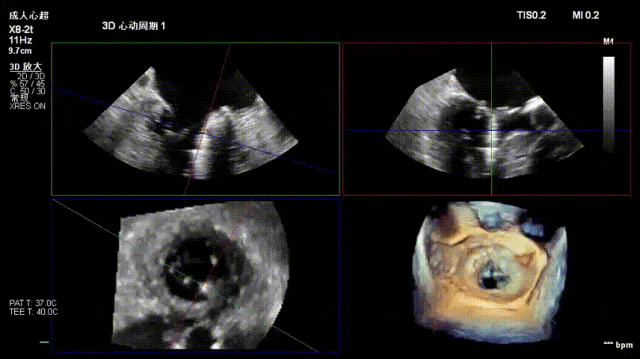

术前经食道超声显示:二尖瓣C1、P1区脱垂,重度关闭不全,彩色多普勒提示大量二尖瓣反流。术前瓣口面积MVA约5cm²,瓣环前后径AP约36.9mm,前叶A1约26mm,后叶P1约15.2mm。

患者全麻后仰卧位,常规消毒铺巾,置入下食道超声探头。于左前胸第五肋间做小切口,暴露心尖,全身肝素化后,心尖穿刺,逐步送入二尖瓣夹系统。术中在超声引导下,分别于C1及A1/P1区植入2枚ValveClamp®二型(MVC-Ⅱf)二尖瓣夹,夹合后超声显示二尖瓣反流明显减轻,随即释放夹子。术后置左侧胸腔引流管1根,逐层关闭胸壁,患者顺利转入ICU观察。

术后即刻反流降为少量,剩余瓣口面积2.57cm²,平均跨瓣压差2mmHg。

术后复查超声心动图显示:二尖瓣轻度返流,三尖瓣中度返流,二尖瓣可见金属夹回声,启闭正常;各心室大小正常,升主动脉不宽,主瓣回声增强,启闭良好;二尖瓣舒张期峰值流速1.4 m/s,功能面积2.1 cm²,跨瓣平均压差约4 mmHg。